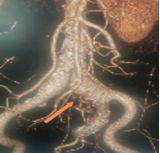

术前CT重建

如何在根治动脉瘤的同时,保住关键的髂内动脉血供?这成为手术成败的核心。经CTA评估,患者左髂总动脉直径超出标准IBD支架适配范围,无法直接植入;但其腹主动脉结构正常,肠系膜下动脉(IMA)却相对粗大,覆膜支架置入后可能会出现Ⅱ型内漏。面对这一复杂解剖挑战,杜长江团队创新制定个体化方案:先行弹簧圈栓塞肠系膜下动脉,再植入腹主动脉覆膜支架主体,巧妙利用其左髂支作为平台,完成IBD系统植入,从而重建并保留左髂内动脉血流。